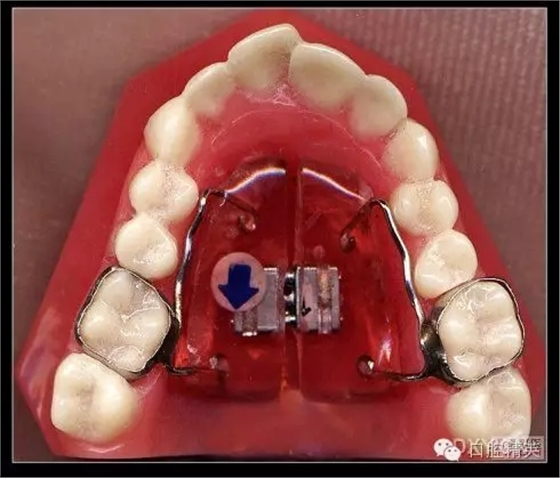

三、擴(kuò)弓器

很多牙列不齊常伴隨牙弓過窄,所以擴(kuò)弓器是正畸醫(yī)生的好伙伴,它可以以多種形態(tài)和您見面。